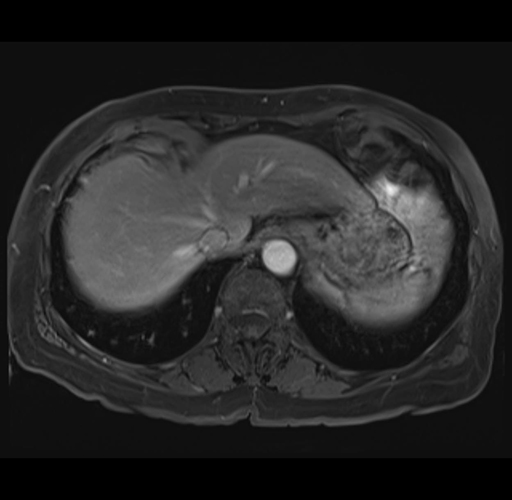

MRI T1